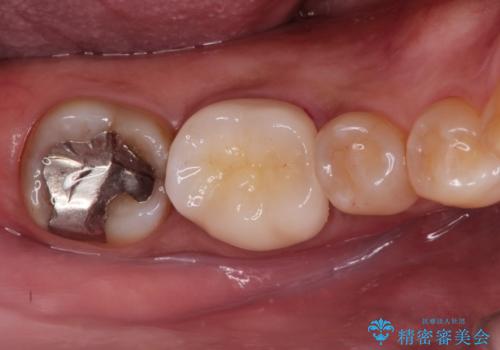

奥歯が痛い。精密根管治療〜オールセラミッククラウン

- 1週間前から冷たいもので強い持続痛を感じることを主訴に来院されました。

歯髄診断と痛みの再現により原因歯を特定し、症候性不可逆性歯髄炎の診断となりました。

根管治療〜オールセラミッククラウン(エクセレント)の治療を行なっております。